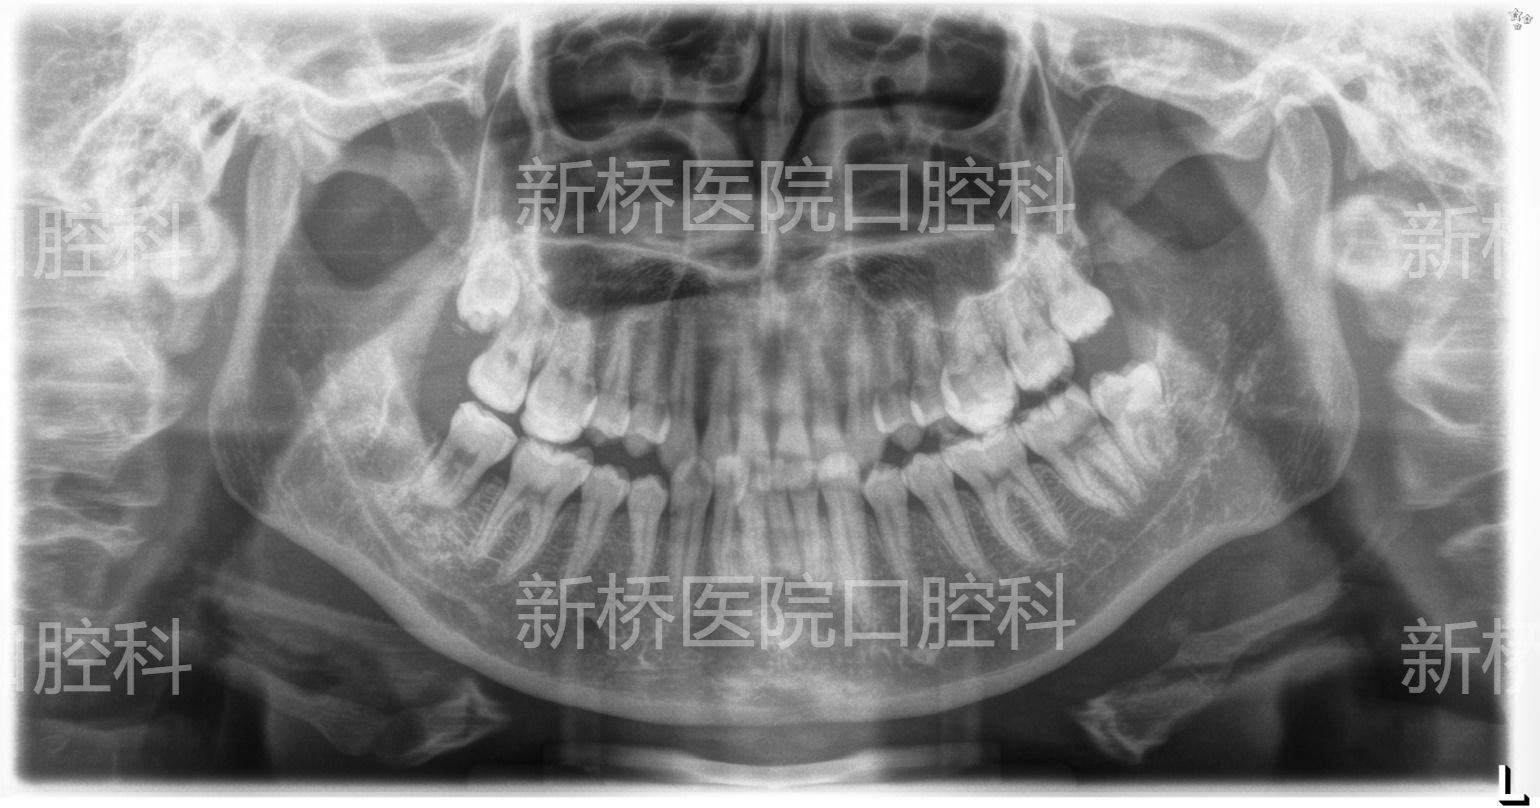

自体牙移植(auto transplantation , ATT) : 自体牙移植是将牙从一个位置移植到同一个体的另一位置,包括将埋伏、阻生、或萌出牙转移到其他缺牙部位牙槽窝内或手术制备的牙槽窝内。

本例采用3D数字化打印技术,术前模拟牙槽窝修整部位,术中用3D打印等比树脂牙试植,做到精准高效制备植入窝,减少供牙离体时间,减少供牙反复植入次数,极大减少供牙牙周膜损伤。